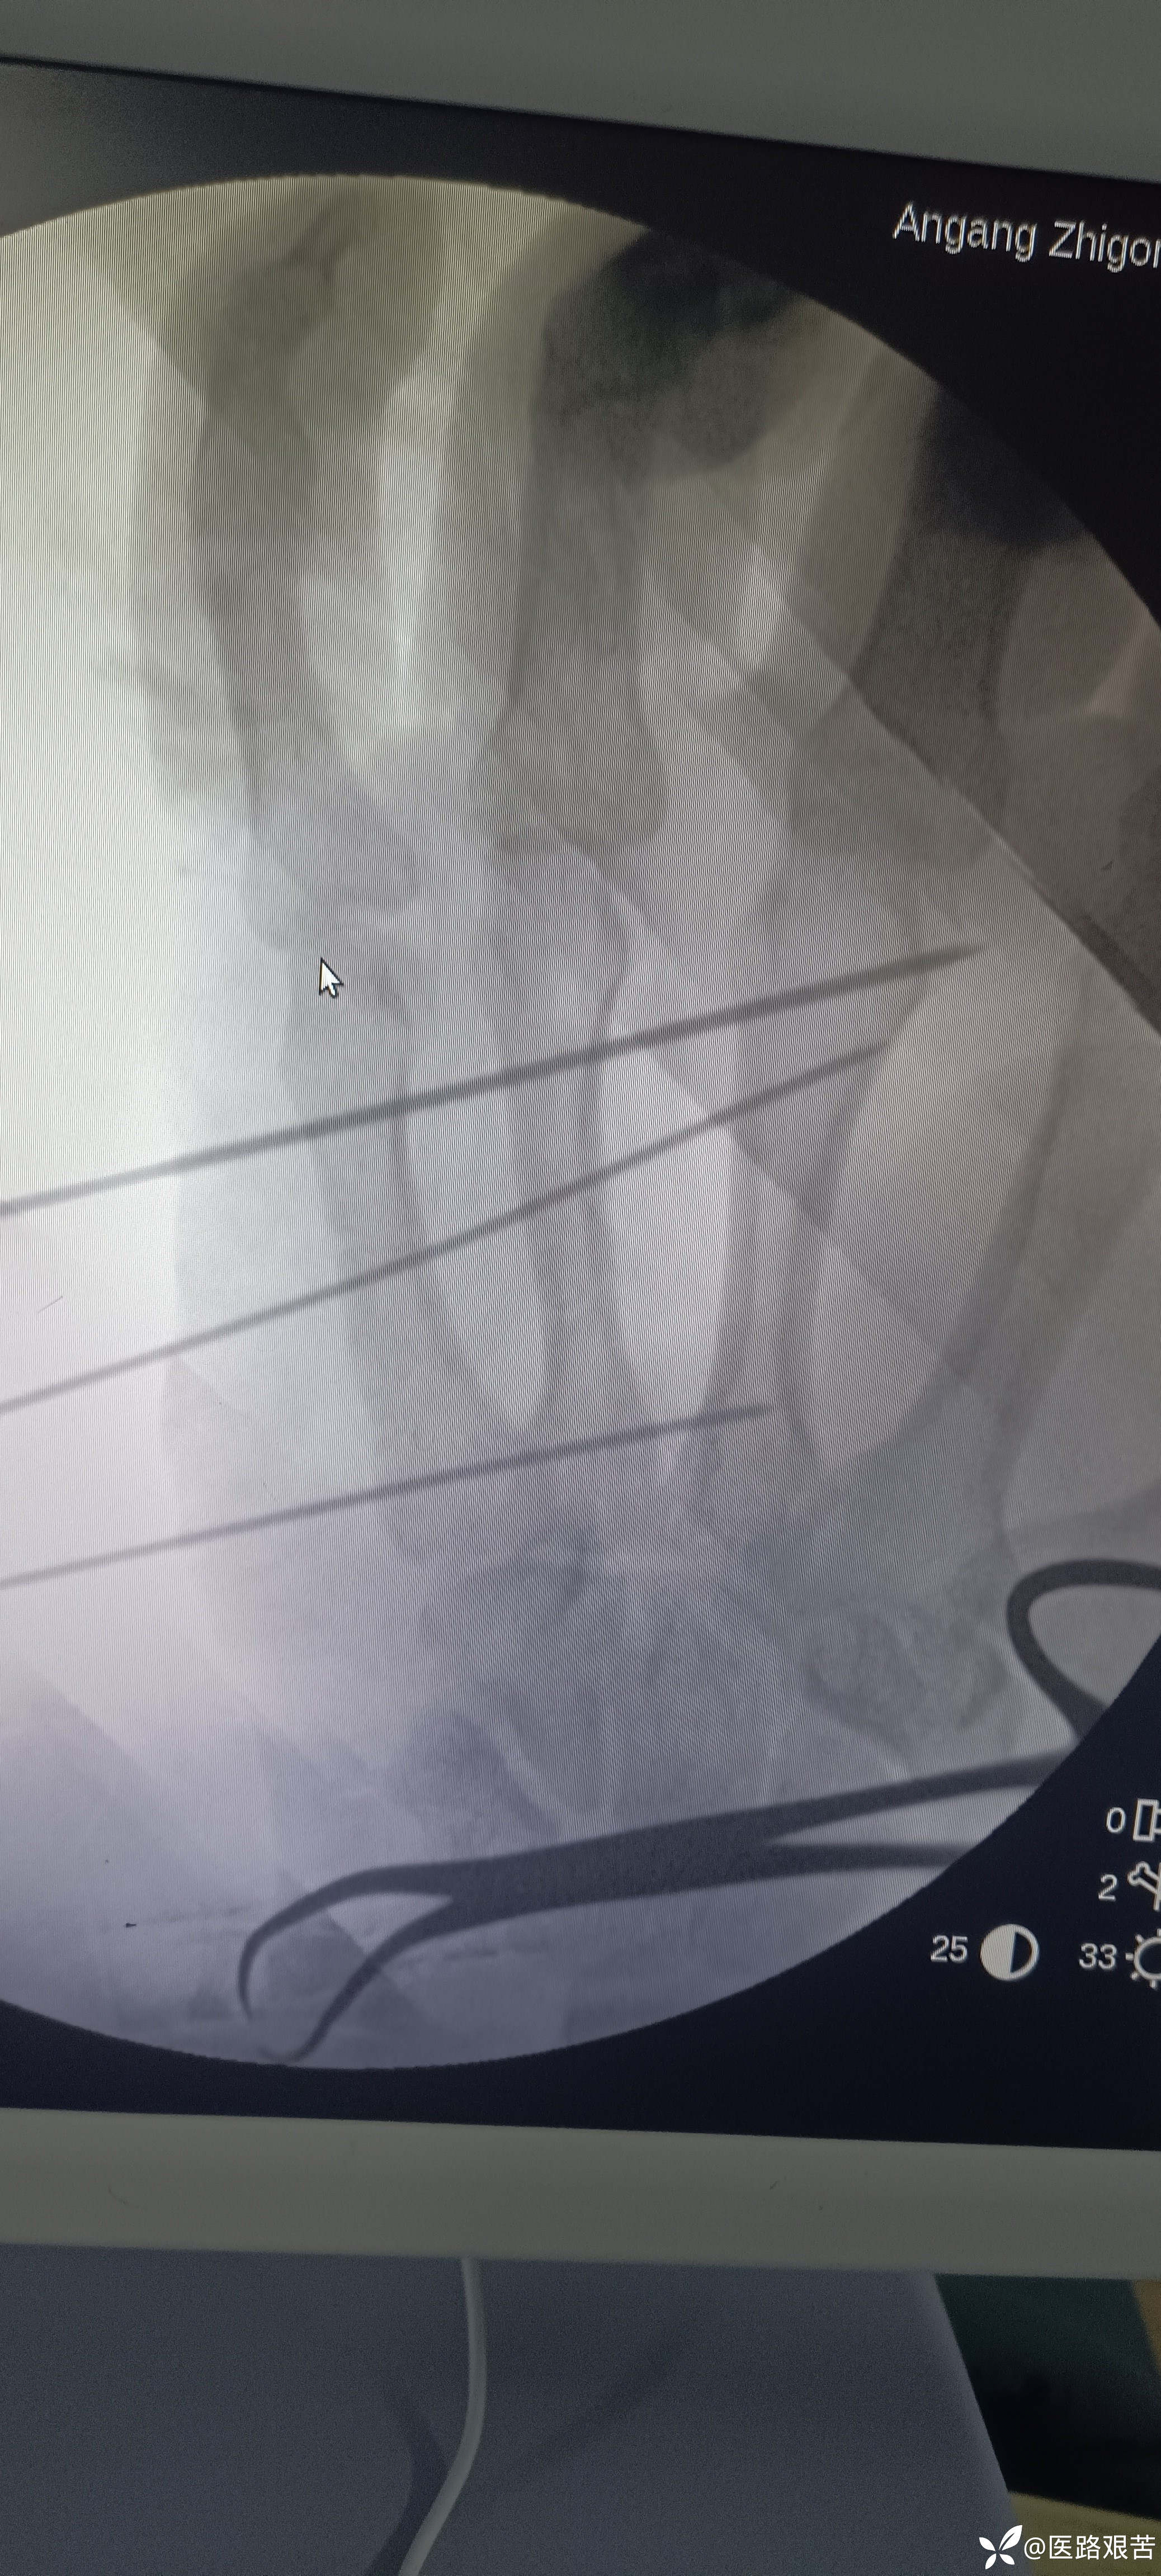

患者,男,32岁,外伤摔倒致右手第四掌骨骨折,伤后1天就医,手法复位石膏固定后,表示骨折立线正,可接受,愈合时间稍长,患者要求解剖复位,并希望早日活动。

手法复位后